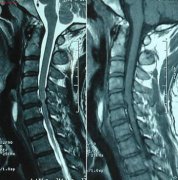

• 成都强直性脊柱炎诊断的一些办法

• 成都强直性脊柱炎的检查方法你知道吗